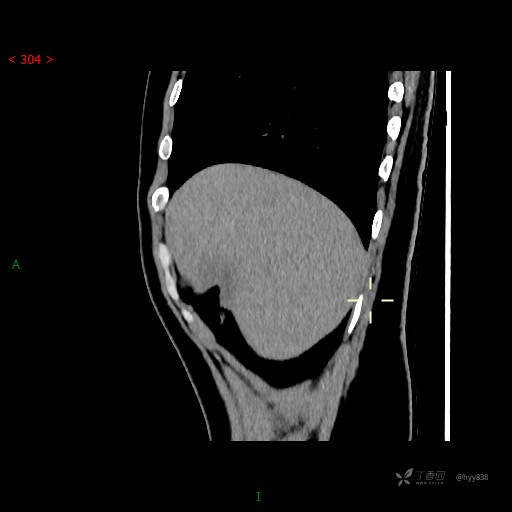

年轻男性,肝脏孤立结节、邻近包膜如此内陷,不知“坑”为何物---(结果公布)

简要病史: 患者1月余出现腰背部疼痛,以夜间疼痛为甚,伴双下肢胀痛,无腹胀、腹痛,无咳嗽、咳痰,无头晕、头痛等症状,门诊超声提示肝结节状占位

肝脏CT平扫

增强动脉期

门脉期

延迟期